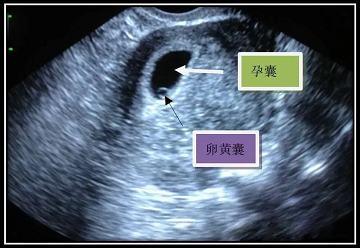

妊娠囊(医学上称为“妊娠囊”)是妊娠早期胚胎发育的第一个可见结构,是胚胎发育的“初始容器”:外层是滋养层细胞(未来发育成胎盘和胎膜),包裹着原始胚胎组织(未来胎儿分化)和羊水(为胚胎提供缓冲和保护)。一般来说,它出现在怀孕的5-6周。

4、内部结构:卵黄囊、胎芽、胎心的出现顺序

•当孕囊可以在B超中看到时,几乎是卵黄囊即将出现时,呈“呈”状O“类型,直径3-6毫米。卵黄囊是确定宫内妊娠的标志(如果平均直径>20毫米,无卵黄囊,则可视为枯萎妊娠囊,也称为空妊娠囊),其数量可用于判断妊娠的数量。

•怀孕6-7周后,胎芽会出现在卵黄囊旁(最初像小海马一样的结构),胎心搏动可以检测到(频率约为110-160次/分)。这是判断“活胎”的核心标志。